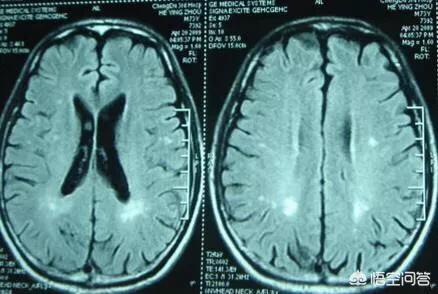

厳密に言えば、ラクナ脳梗塞とは、大脳半球や脳幹の深部にある細い貫通動脈が、長期にわたる様々な危険因子の関与、特に高血圧の影響によって血管内腔の閉塞を起こし、小さな梗塞巣を形成したものである。例えるなら、脳を白い紙とすると、ラクナ脳梗塞は白い紙の上に撒かれたゴマで、非常に小さいがすでに存在している。

空洞性脳梗塞は、大脳半球および脳幹の深部白質に発生する虚血性微小脳梗塞である。梗塞巣は不規則な円形、卵形、または細長い形をしており、その直径は数ミリである。以前は、この現象はヒトの脳の病理解剖時にのみ検出されていた。CTやMRIが普及し、技術が進歩するにつれて、ラクナ脳梗塞が発見される確率が高くなった。

脳梗塞とは、脳血液循環障害や虚血・低酸素症によって脳組織が限定的に虚血軟化または壊死することをいう。ラクナ型脳梗塞は大脳基底核や脳橋の小貫通枝にある小さなラクナ病巣が主な原因で、病巣のほとんどは15mm以下の小さな範囲である。小動脈硬化、閉塞、アテローム性動脈硬化症、心臓塞栓症は脳梗塞の最も重要な危険因子である。

また、無症状のラクナ脳梗塞が1~2個あっても、現時点では健康への影響はほとんどないことも重要である。しかし、ラクナ脳梗塞が多発すると、片麻痺や失語症などの典型的な症状がなくても、記憶障害や反応速度の低下などの認知障害を起こすことがあります。したがって、無症候性ラクナ脳梗塞が発見された場合には、より重篤な結果を避けるために、自分の危険因子を注意深く検索し、厳格に管理する必要がある。